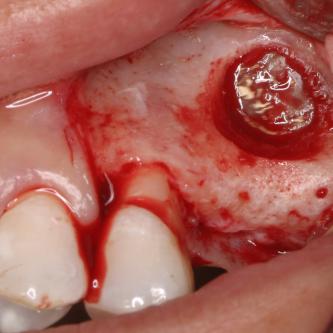

Exemple 14: Un petit puits d'accès est créé afin d'atteindre le sinus, notez la membrane sinusienne.

Exemple 14: La fine membrane sinusienne est relevée, puis de l'os mélangé à de l'os artificiel est introduit dans la cavité.